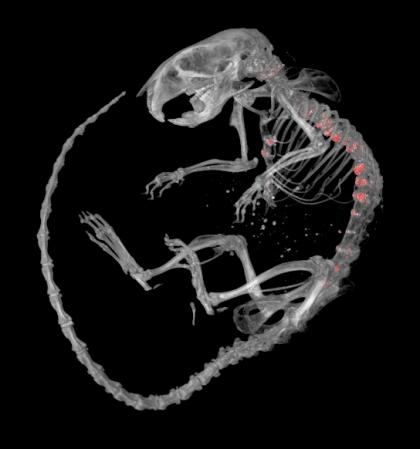

Micro-CT image of mouse skeleton, showing excessively mineralized lesions (in red) along the spinal column and sternum (breastbone).

According to The Arthritis Society, the second most common form of arthritis after osteoarthritis is "diffuse idiopathic skeletal hyperostosis" or DISH. It affects between six and 12 percent of North Americans, usually people older than 50. DISH is classified as a form of degenerative arthritis and is characterized by the formation of excessive mineral deposits along the sides of the vertebrae in the neck and back. Symptoms of DISH include spine pain and stiffness and in advanced cases, difficulty swallowing and damage to spinal nerves. The cause of DISH is unknown and there are no specific treatments.

Changes in the backbone of these mice were characterized by an interdisciplinary team, which included graduate student, Sumeeta Warraich, technician, Diana Quinonez, postdoctoral fellow, Hisataka Ii, imaging scientists Maria Drangova and David Holdsworth, and skeletal biologist, Jeff Dixon. Their findings established that spinal mineralization in these mice resembles DISH in humans and point to a role for adenosine in causing abnormal mineralization in DISH.